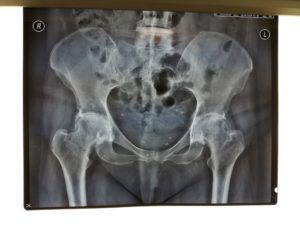

Περίπτωση ταυτόχρονης αρθροπλαστικής AMIS για αμφοτερόπλευρη οστεοαρθρίτιδα Ισχίου

Η ασθενής είναι 56 ετών και υπέφερε από οστεοαρθρίτιδα και των δύο ισχίων με έντονο πόνο και σοβαρή δυσκολία στη βάδιση.